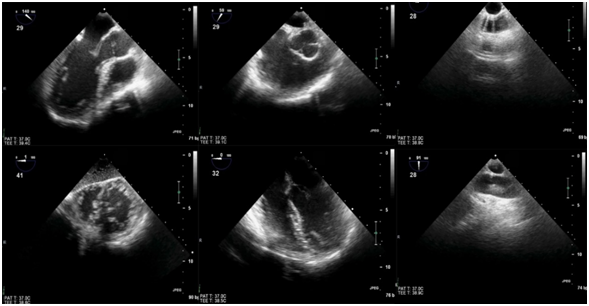

截至目前,TEE-FOCUS包括6个基本切面(图5-6),其中有4个关于心脏的基本切面和2个关于大血管的基本切面:1. 左心室长轴切面,2. 右心室流入流出道切面,3. 降主动脉短轴切面,4. 经胃底心室短轴切面,5.食管中段四腔心切面,6.升主动脉长轴切面(新增)。TEE-FOCUS中的6个基本切面具体评估要点如表2所示。对于非心脏手术TEE-FOCUS也包括6个基本切面,不同之处是将升主动脉长轴切面替换为食管中段双腔静脉切面。

什么叫超声容积探头围手术期经食管超声心动图监测操作的专家共识(可下载)_https://www.jmylbn.com_新闻资讯_第38张

图5  TEE-FOCUS 6个基本切面的2D图像

什么叫超声容积探头围手术期经食管超声心动图监测操作的专家共识(可下载)_https://www.jmylbn.com_新闻资讯_第39张

图6TEE-FOCUS中的6个基本切面的模型切面示意图